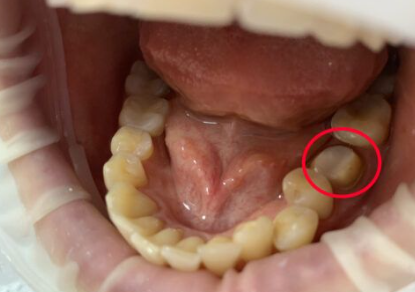

Установка металлокерамической коронки

Перелом зуба глубоко под десну.

Применена современная техника «растяжения тканей» – оптимальное формирование десны с применением временной конструкции.

Окончательный вид – металлокерамическая коронка

Доктор: Репьева Марина Владимировна